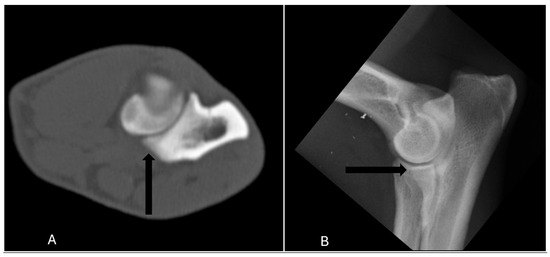

Medical imaging is a vital component in veterinary orthopaedics, offering essential insights into the diagnosis, treatment, and management of musculoskeletal disorders across various species. With the continuous advancement of veterinary medicine, the application of precise imaging techniques, such as radiography (xR), ultrasound (US), computed tomography (CT), and magnetic resonance imaging (MRI), has gained increasing prominence in both clinical practice and research. These modalities enable accurate diagnoses of orthopaedic pathologies, enhancing patient outcomes while also advancing our understanding of animal biomechanics, injury mechanisms, and recovery dynamics.

This Special Issue, “Medical Imaging in Veterinary Musculoskeletal Diagnosis”, aims to deepen and update knowledge on the importance of orthopaedic imaging diagnosis in veterinary medicine. Therefore, the inclusion of clinical or experimental research work is encouraged. The research can be based on any type of medical imaging modality (e.g., xR, US, CT, MRI), in different veterinary species: companion animals, species of livestock interest, sport animals, or exotic or wild animals. Through a collection of research articles, reviews, and expert opinions, this Special Issue will contribute as an important resource for veterinarians and researchers on orthopaedic veterinary imaging diagnosis.